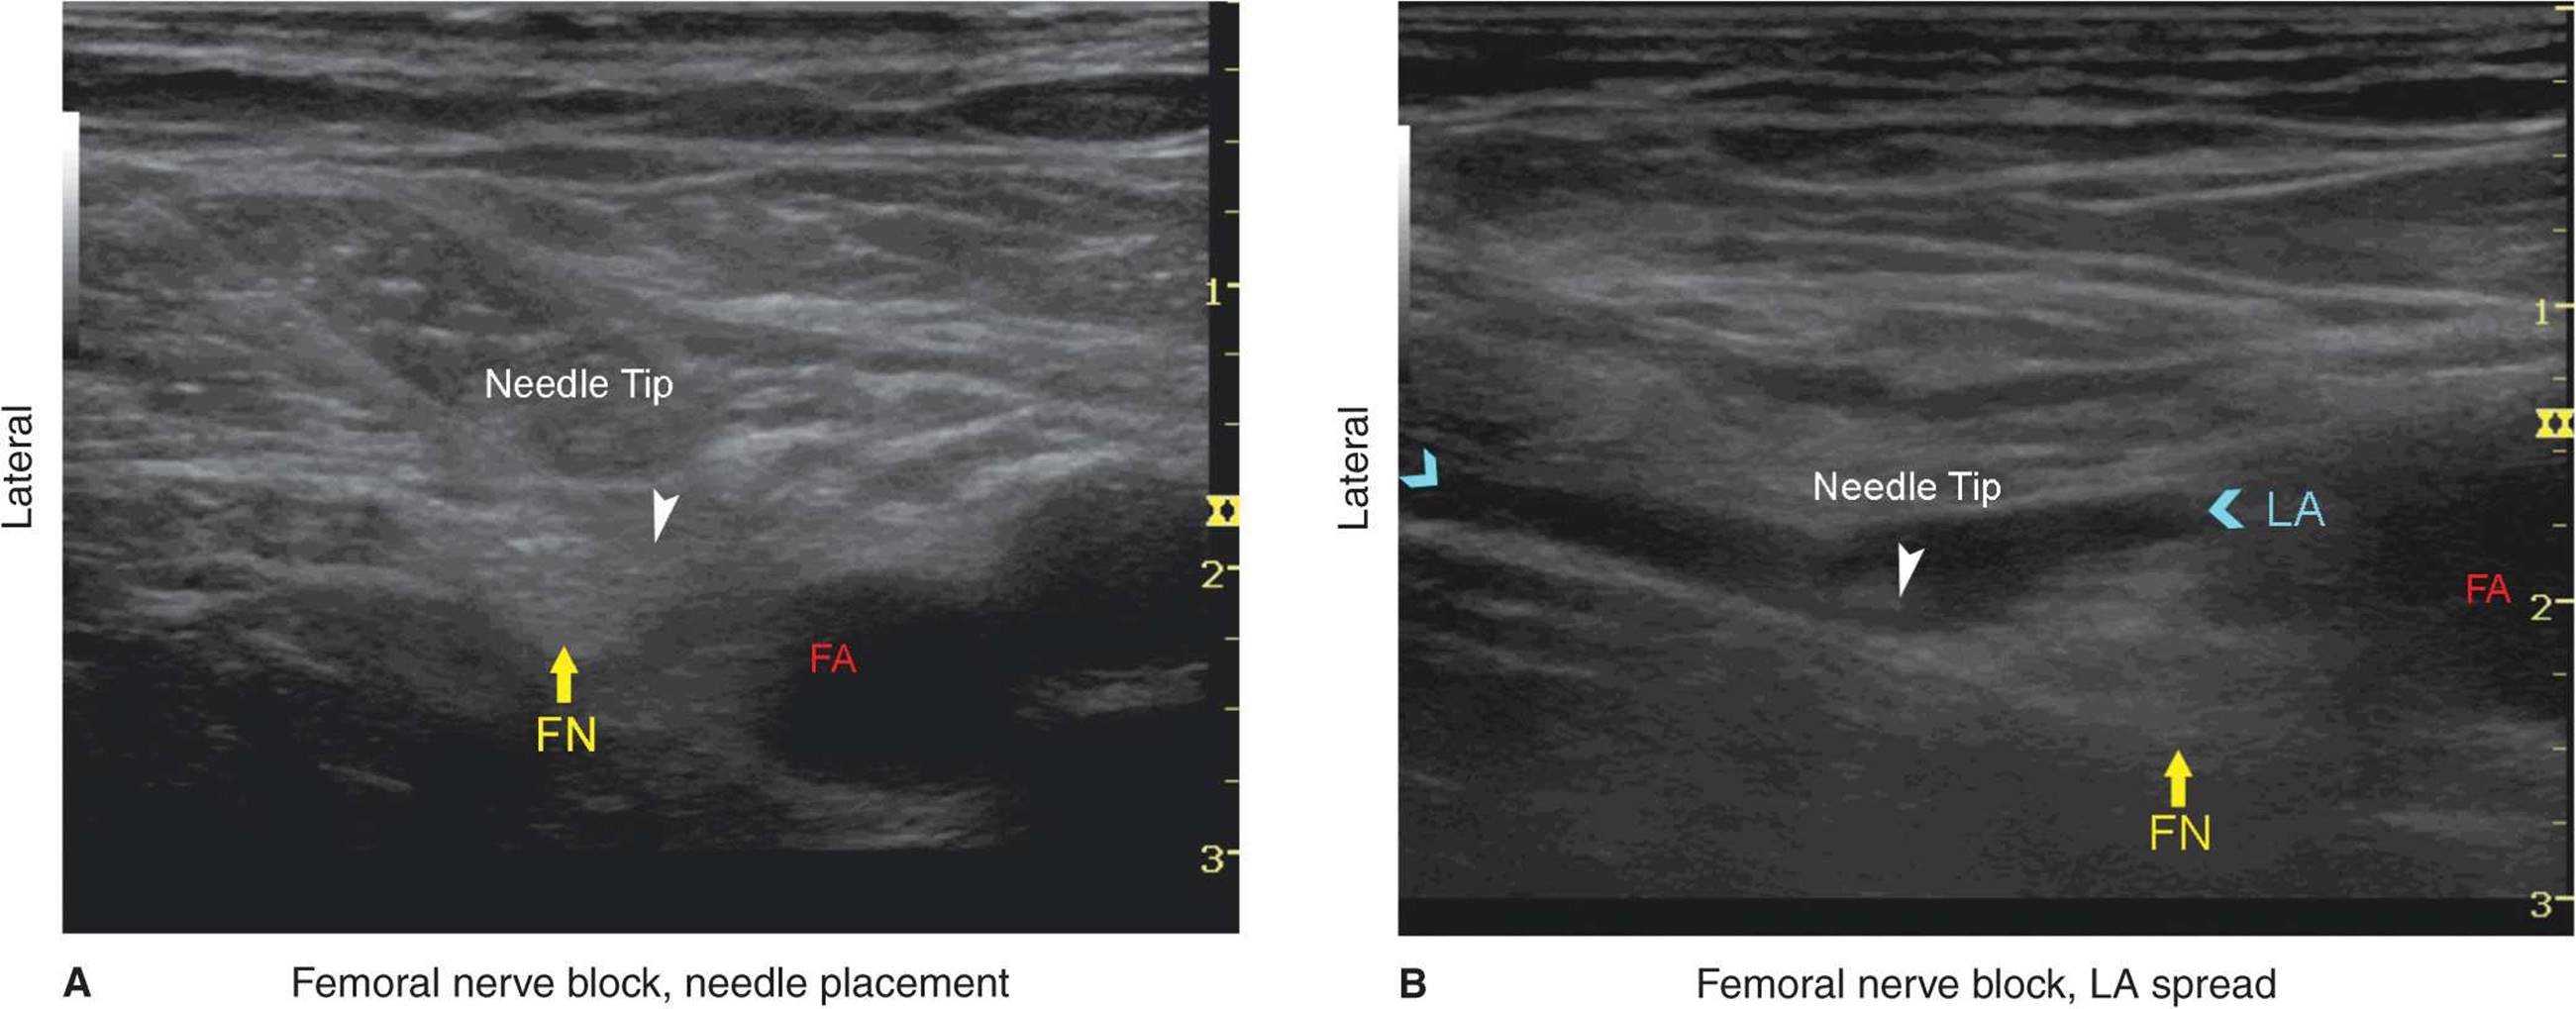

With the patient in the supine position, the skin over the femoral crease is disinfected and the transducer is positioned to identify the femoral artery and/or nerve (Figure 35-4). If the nerve is not immediately apparent lateral to the artery, tilting the transducer proximally or distally often helps to image and highlight the nerve from the rest of the iliopsoas muscle and the more superficial adipose tissue. In doing so, an effort should be made to identify the iliopsoas muscle and its fascia as well as the fascia lata because injection underneath a wrong fascial sheath may not result in spread of the local anesthetic in the desired plane. Once the femoral nerve is identified, a skin wheal of local anesthetic is made on the lateral aspect of the thigh 1 cm away from the lateral edge of the transducer. The needle is inserted in-plane in a lateral-to-medial orientation and advanced toward the femoral nerve (Figure 35-5). If nerve stimulation is used (0.5 mA, 0.1 msec), the passage of the needle through the fascia iliaca and contact of the needle tip with the femoral nerve usually is associated with a motor response of the quadriceps muscle group. In addition, a needle passage through the fascia iliaca is often felt as a “pop” sensation. Once the needle tip is witnessed adjacent (either above, below, or lateral) to the nerve (Figure 35-6), and after careful aspiration, 1 to 2 mL of local anesthetic is injected to confirm the proper needle placement (Figure 35-7). When injection of the local anesthetic does not appear to result in a spread close to the femoral nerve, additional needle repositions and injections may be necessary.

In an adult patient, 10 to 20 mL of local anesthetic is adequate for a successful block (Figure 35-8A and B). The block dynamics and perioperative management are similar to those described in Chapter 21.

FIGURE 35-8. (A) An actual needle path to block the femoral nerve (FN). (B) Spread of the local anesthetic (LA) within two layers of the fascia iliaca to encircle the femoral nerve (FN). FA, femoral artery.